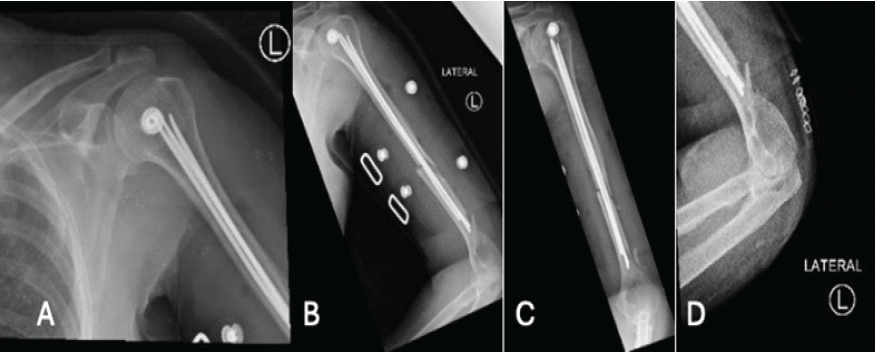

The patient had no other injuries and was neurovascularly intact on presentation. She was an independent ambulator. The patient was treated with a coaptation splint in the emergency room, with plans for operative fixation the next day. Following a pre-operative assessment, the patient was scheduled for closed reduction with internal fixation under general anesthesia. In the supine position, with a radiolucent arm table, without a tourniquet. Landmarks were identified, and a 3–5 cm incision was taken from the lateral epicondyle. The lateral cortex was perforated with an awl, and entry was established and confirmed under fluoroscopy in both anteroposterior (AP) and lateral views. An adequate nail was then fixed in a universal chuck with a T-handle and advanced with oscillating hand movements until it reached the fracture site. The nail was introduced into the proximal fragment by indirect manipulation of the fragment under fluoroscopy. Subsequent manual advancement of the nail was carefully done, passing the fracture site until finally resting at the humeral head. Same steps were taken to reach a total of 3 elastic nails of size 3 mm filling the medullary canal. Following closure, the patient was placed in a functional brace with a non-weight-bearing (NWB) status of the left upper extremity (Fig. 2).

Figure 2: Humerus fracture post-fixation. (a) Anterior-posterior (AP) X-ray of the shoulder post-fixation, (b) lateral X-ray of the humerus post-fixation, (c) AP X-ray of the humerus post-fixation. (d) Lateral X-ray of the distal humerus post-fixation.